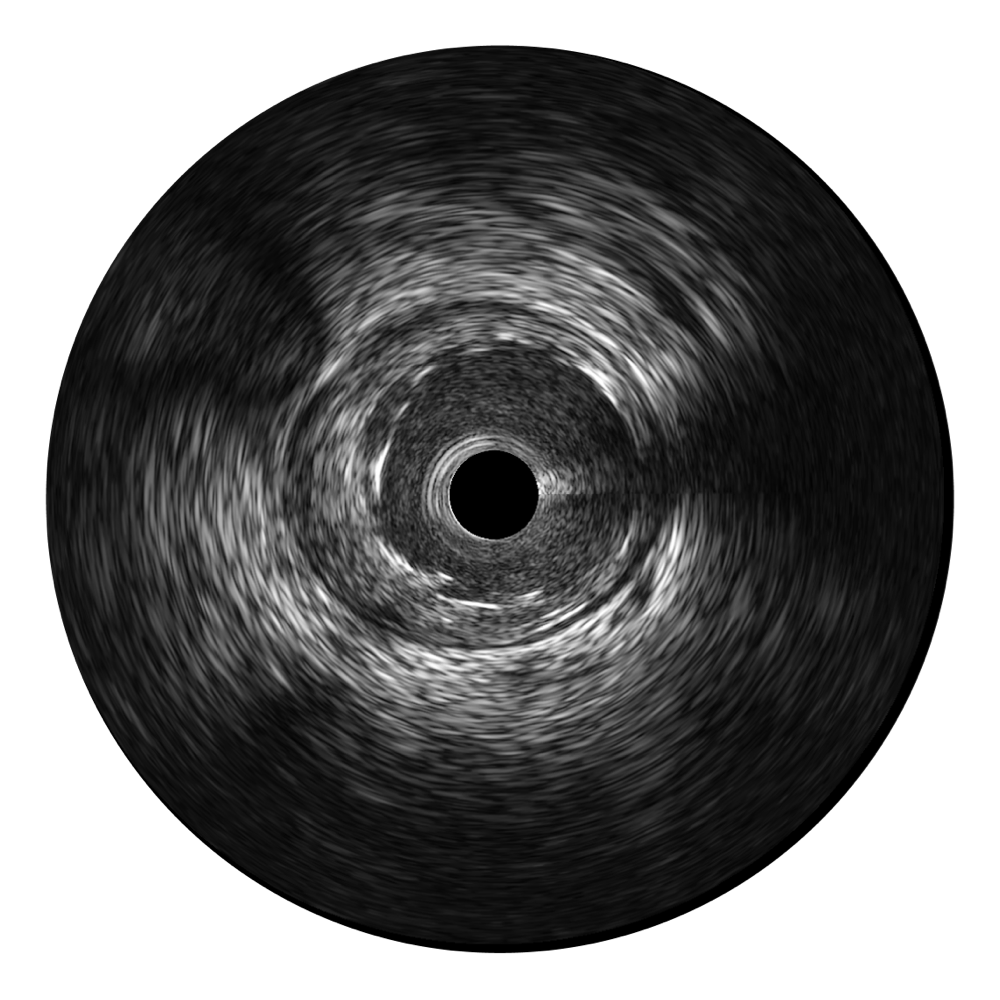

百老汇电子游戏官网宽频IVUS图像

对比传统IVUS导管成像,百老汇电子游戏官网宽频IVUS图像的近场支架梁显影更细腻,远场中膜外血管仍清晰可辨,兼顾远中近,兼顾分辨力与穿透深度